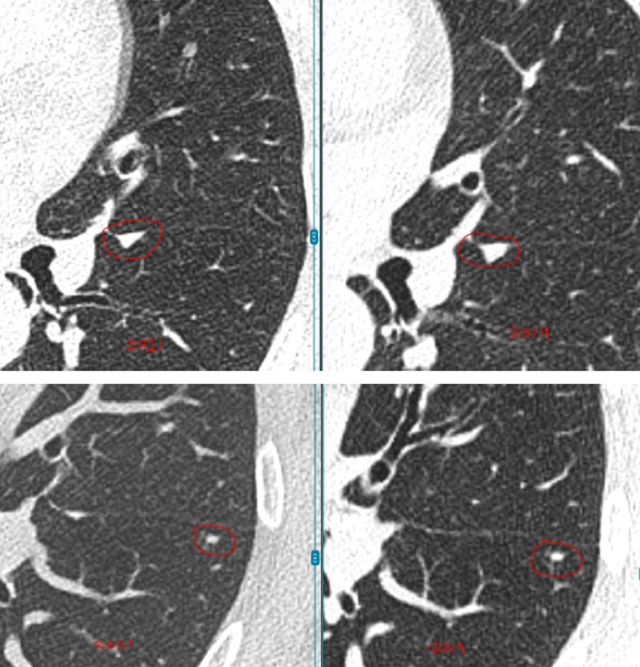

具体来看,右肺有一个磨玻璃结节(约4mm),左肺还有两个实性结节(约5mm、3mm)。

之后的4年里,这3枚小结节都没有什么变化,这让她逐渐放下心来。

然而在随后的一次复查中,CT结果显示磨玻璃结节“密度略微增加”,而且又新出现了一枚3mm的小结节。

“先看左肺这两枚实性结节,它们在这几年一直很稳定,没有明显增大,形态也没有变化。像这类稳定超过3年的小实性结节,良性可能性超过了99%。从片子上看,它们更像是肺部之前因为旧损伤留下的痕迹。”L教授说。

关于右肺的4mm磨玻璃结节,L教授对比了新旧影像,并不认为它在恶化。

“这一枚,是您现在担心的,对吗?因为报告里提到它的密度比以前稍微高了一点。但从影像上看,这种变化还是非常轻微的,目前还没有达到让我们怀疑它正在明显恶化的程度。它确实值得继续随访,但至少以现在这个状态,还谈不上需要立刻处理,更不意味着已经朝着癌的方向快速发展。”L教授说。

关于右肺新出现的那枚大约3mm的磨玻璃结节,L教授同样为林女士进行了详细解释。

他指出,很多人一听到出现新发结节,马上会非常紧张,觉得可能是冒出了不好的东西。其实不是这样。

“像这么小、这么淡的磨玻璃结节,在临床上很常见,很多时候更像是一过性的炎性反应,可能和轻微感染甚至短期肺部状态变化有关。有些结节过一段时间复查,自己就消失了。所以对这枚结节,我目前更倾向于把它看作一个温和的、需要观察的信号,而不是一个必须马上干预的问题。”L教授说。

L教授总结道:“总体来看,您现在这4枚结节都还很小,而且没有哪一枚表现出必须马上手术或活检的证据。左肺两枚实性结节长期稳定,右肺原有的磨玻璃结节虽然密度略有变化,但幅度很小,新发的3mm磨玻璃结节也更像炎性改变。换句话说,它们都还没有到‘该切的时候’。现阶段继续按计划随访,是安全的,也是更合理的做法。”